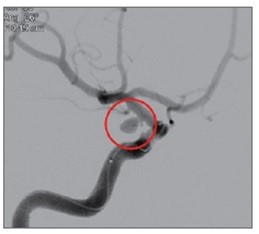

![]() |

| ▲ |

뇌동맥류로 인해 부풀어 오른 혈관이 터지면 뇌출혈이 생긴다. 이 경우 사망 위험이 크게 증가하고 뇌에 영구적 손상이 가해져 언어장애, 운동장애 등이 유발된다.